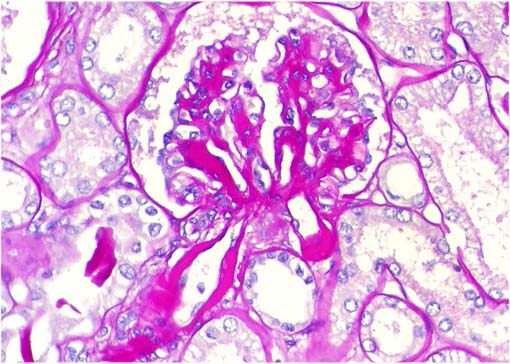

Figura 4.

Tricrómico de Masson, X400.